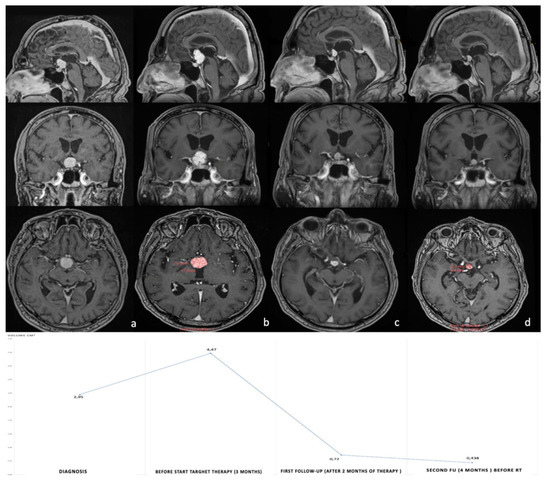

The very encouraging results obtained with the combined BRAF and MEK inhibitors in patients with recurrent and aggressive PCPs is opening new frontiers for a neo-adjuvant approach to this condition. Calvanese et al. first reported a case of a solid third ventricular mass presenting with headache, psychiatric disorders, and left optic atrophy [16]. The authors decided to perform a trans-ventricular neuro-endoscopic biopsy, revealing a PCP harboring the conventional BRAF V600E mutation. The patient underwent the combined targeted therapy with dobrafenib and trametinib, with a volume reduction of 90% at 4 months follow-up, followed by radiotherapy at the end of oncological treatment (Figure 2). To date, this is the only case of a PCP managed by a neo-adjuvant approach. Obviously, obtaining a diagnosis of PCP by non-invasive (or at least minimally invasive) techniques represents a mandatory step to apply a neo-adjuvant treatment. Fujito et al. considered that three preoperative clinical factors could be able to predict the BRAF mutation in PCPs with a high sensitivity and specificity: age above 18 years, a supradiaphragmatic tumor location and absence of intratumoral calcification [62]. However, the administration of such a specific treatment needs a formal diagnosis of BRAF V600E mutated PCP which cannot be fulfilled only with radiological findings. In our original article, we proposed a new algorithm to apply in case of radiological suspicion of PCP, but also in the presence of giant and invasive CPAs with difficult surgical access [16] (Figure 3). In these patients, a tissue sample obtained by different mini-invasive approaches (endoscopic transventricular, endoscopic endonasal or even by mini-craniotomy tailored on the lesion) should be the first option prior to making clinical decisions. This strategy should be considered, even in case of neurological deficit (such as visual impairment), due to the rapid and impressive results in reducing tumor volume offered by oncological treatment. It is important to highlight that medical therapy alone seems to be insufficient in providing a long-term control of the lesion. In other words, the aim of the neo-adjuvant approach should not be “curative” but rather “complementary” to radiotherapy or surgery. Indeed, several reports found that stopping medical treatment after a good initial response could be associated with a non-negligible risk of early tumor recurrence in patients with a previously diagnosed PCP [2,13,14,16,18,19,21,38,39]. Moreover, an excellent long-term tumor control seems to be reached when radiotherapy or radiosurgery are performed at the end of oncological treatment [5,63]. Of course, a lower tumor volume also strengthens the possibility to obtain a gross total resection by surgery [4,16,27,28,64]. Therefore, surgical resection has to be considered, as well as radiotherapy to integrate and complete the ideal management of the patient diagnosed with PCP and initially treated with targeted therapy.

Figure 2.

Post-gadolinium axial, coronal and sagittal T1WI MRI images of the first reported case treated with neoadjuvant BRAF/MEK inhibitor therapy. (a) Post-contrast T1-weighted image shows the large homogeneously enhanced intraventricular mass measuring 19 × 18.5 mm maximal axis and 2.945 cm3 volume. (b) Shows the progression of the intraventricular tumor portion after trans-ventricular endoscopic biopsy (18% of tumor volume). Panels c and d show a dramatic reduction in volume at 2 months (c) and 4 months (d) after commencing combined BRAF/MEK inhibitor treatment. Note the complete resolution of the mass effect on suprasellar neurovascular structures and on the Monro foramen. Volume curve has been reported in the inferior part of the figure. RT, radiotherapy. Taken from with permission: Calvanese, F., et al., Neoadjuvant B-RAF and MEK Inhibitor Targeted Therapy for Adult Papillary Craniopharyngiomas: A New Treatment Paradigm. Front Endocrinol (Lausanne), 2022. 13: p. 882381 [16].